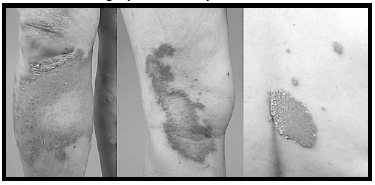

Paciente do sexo feminino, de 56 anos,

procedente de Cuiabá, refere aparecimento de

lesões isoladas em tronco e membros há 1 ano.

Refere que há 3 meses houve crescimento

progressivo das lesões, com acentuação do

eritema. Nega prurido e episódios de febre.